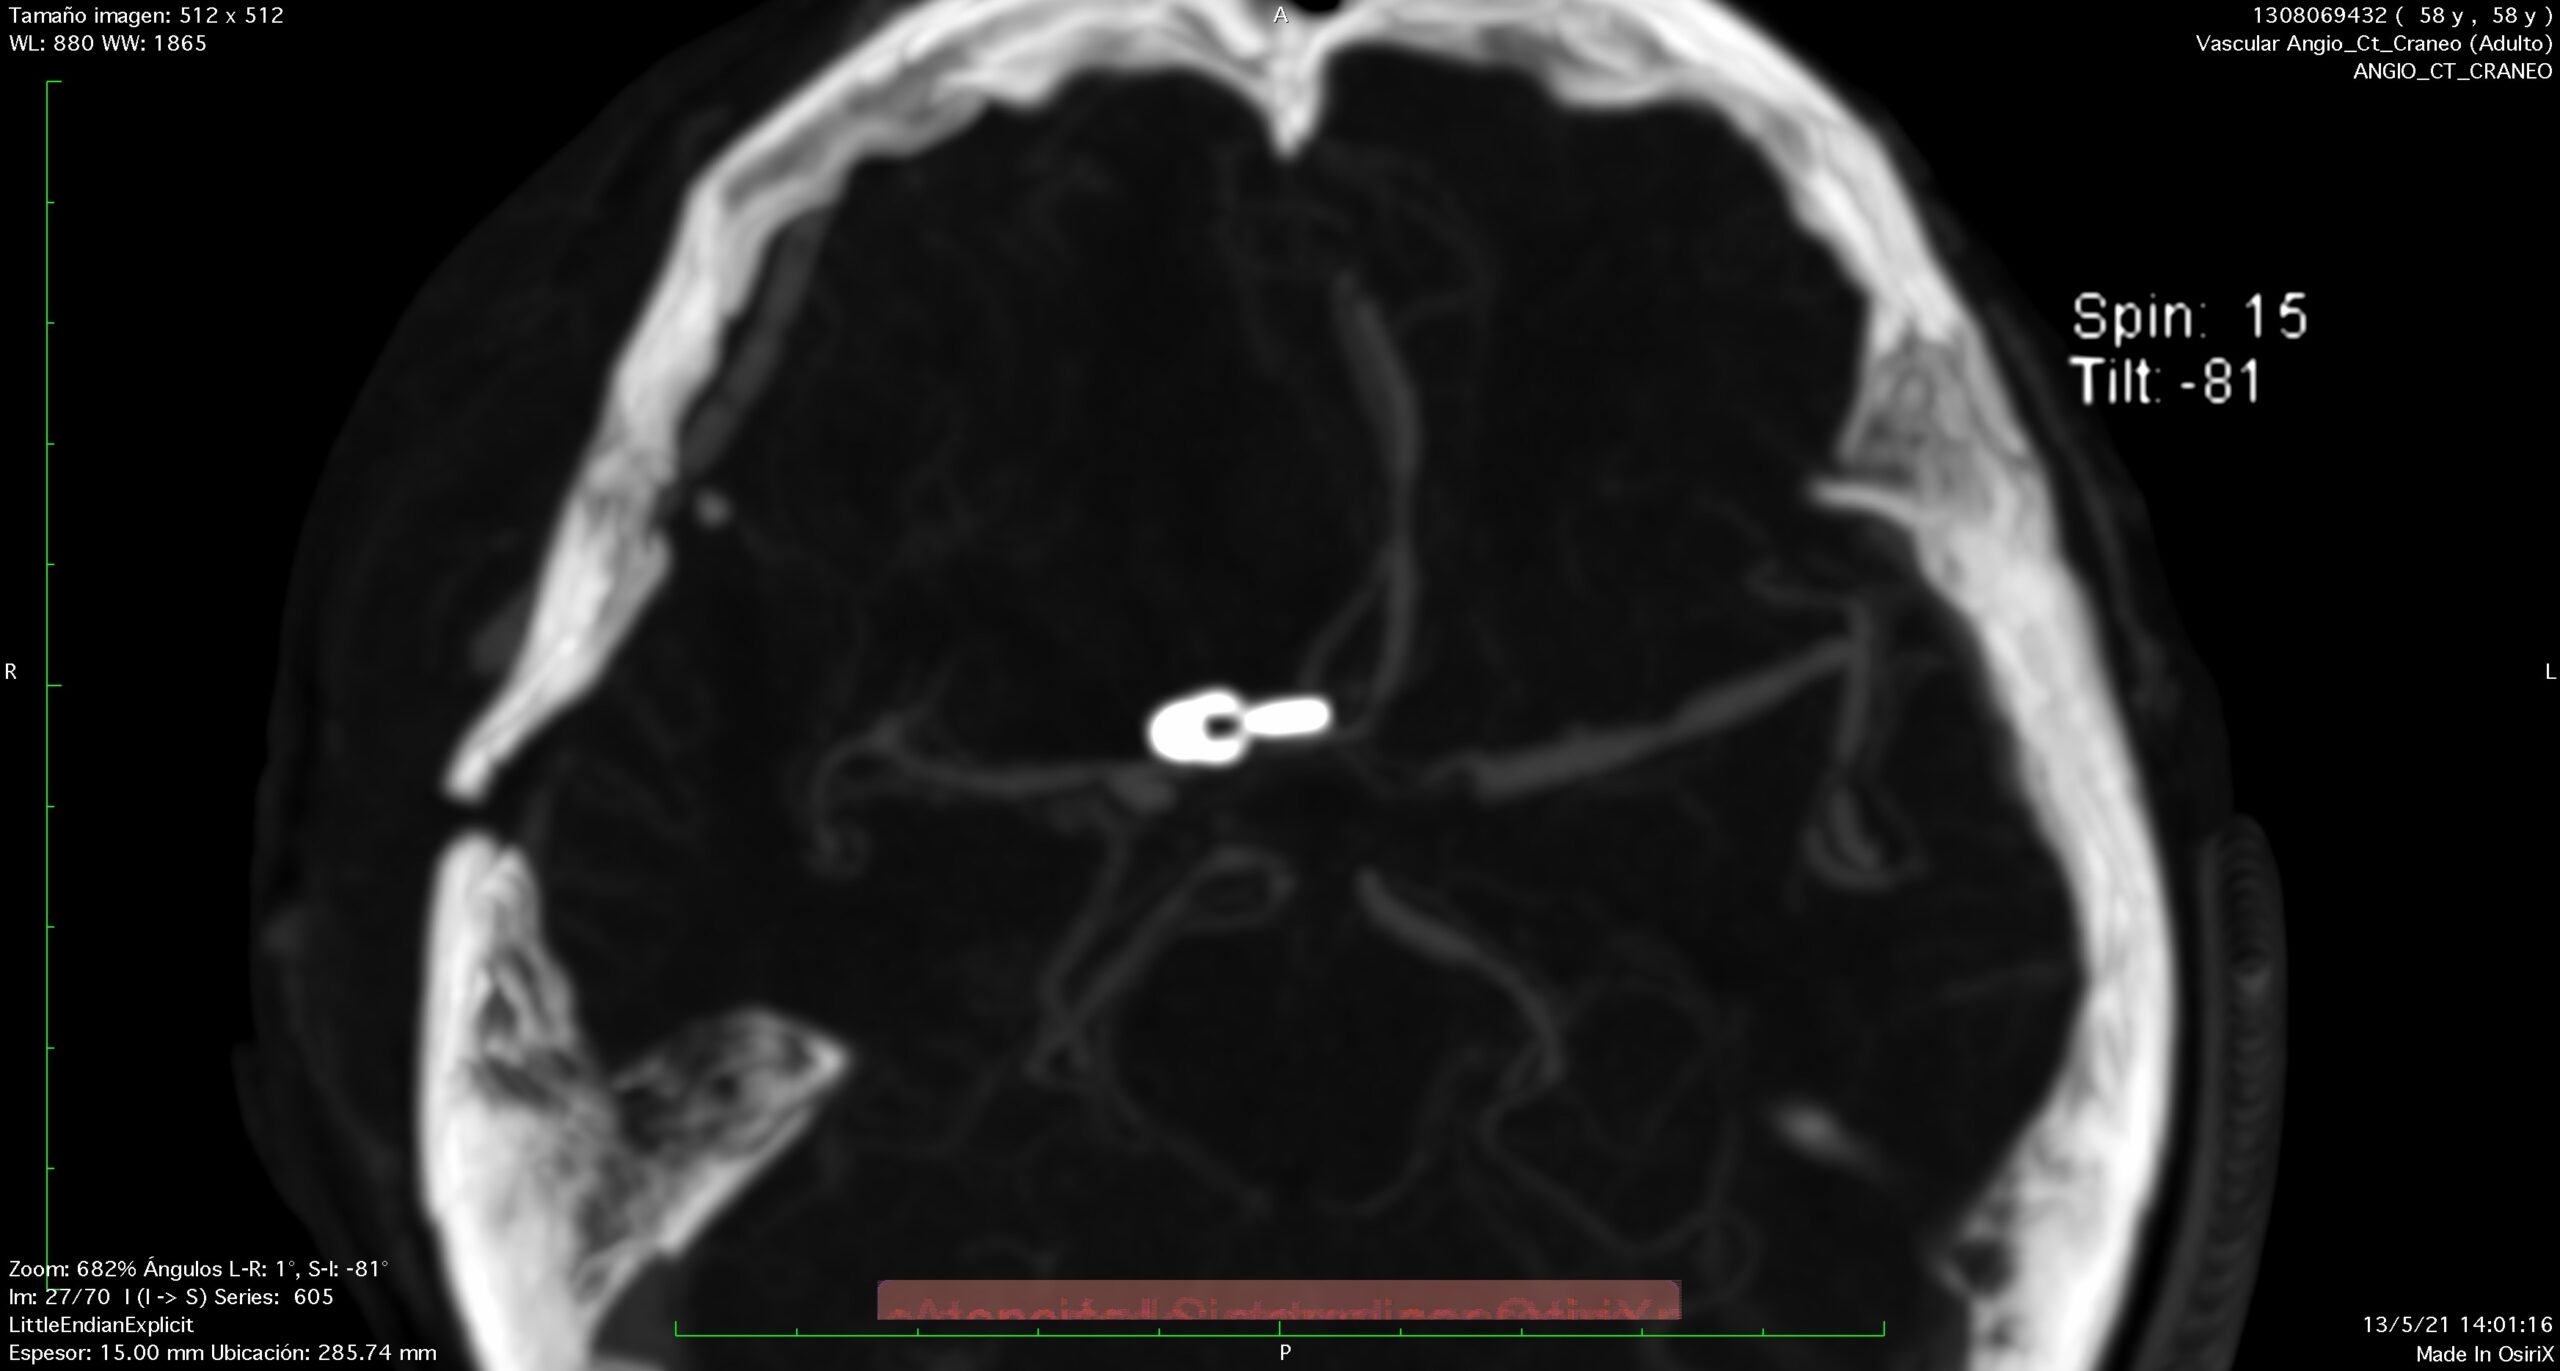

The typical bleeding pattern is seen after aneurysm rupture. The shape and location of the aneurysm can predict its behavior and also determine which treatment is preferred. Alternatively, if the aneurysm has a low risk of rupture or a high surgical risk, we may choose to surveil it with serial imaging. The intervention is designed to block the blood flow into the aneurysm, therefore eliminating the risk of hemorrhage. It can be performed endovascularly – by filling the aneurysm from within (“endovascular coiling”), or by open microsurgical techniques (“clipping”).

Recurrent aneurysm seen near clips

3D brain angiography showing an aneurysm